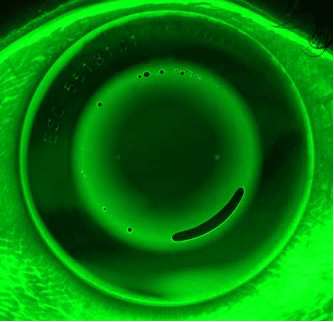

Incomplete reverse curve rings form when a lens fails to align to the peripheral cornea in one meridian. This results in an uneven ring of mid-peripheral steepening, preventing the central fluid pressure from achieving the desired corneal compression. On topography, incomplete reverse curve rings will present as an uneven “bull’s-eye” ring. The reverse curve may be incomplete in only one quadrant (Figure 2) or across an entire meridian (Figure 3).

Such topography patterns can commonly occur without issue and may not require any lens modifications. If the patient’s vision is significantly reduced, consider adjusting the peripheral toricity of the ortho-k design to resolve this issue.